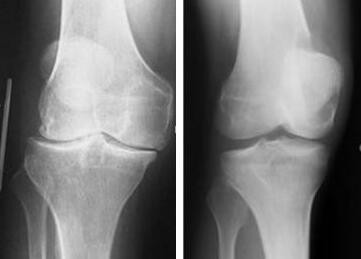

(图:唐先生膝关节肿胀明显,不能正常伸直弯曲,活动受限)

来院后,我院医生杜爱华主任在经过一番了解后,决定先对其进行检查了解病情的原因。检查后发现:抗O是84.4,血沉110/h,加上唐先生的膝关节肿胀明显,不能正常伸直弯曲,活动受限,关节遭受到严重的破坏,关节面边缘模糊不清,诊断为风湿性关节炎。

(图:从x光片上可以明显看出治疗前后的不同,唐先生已恢复正常)